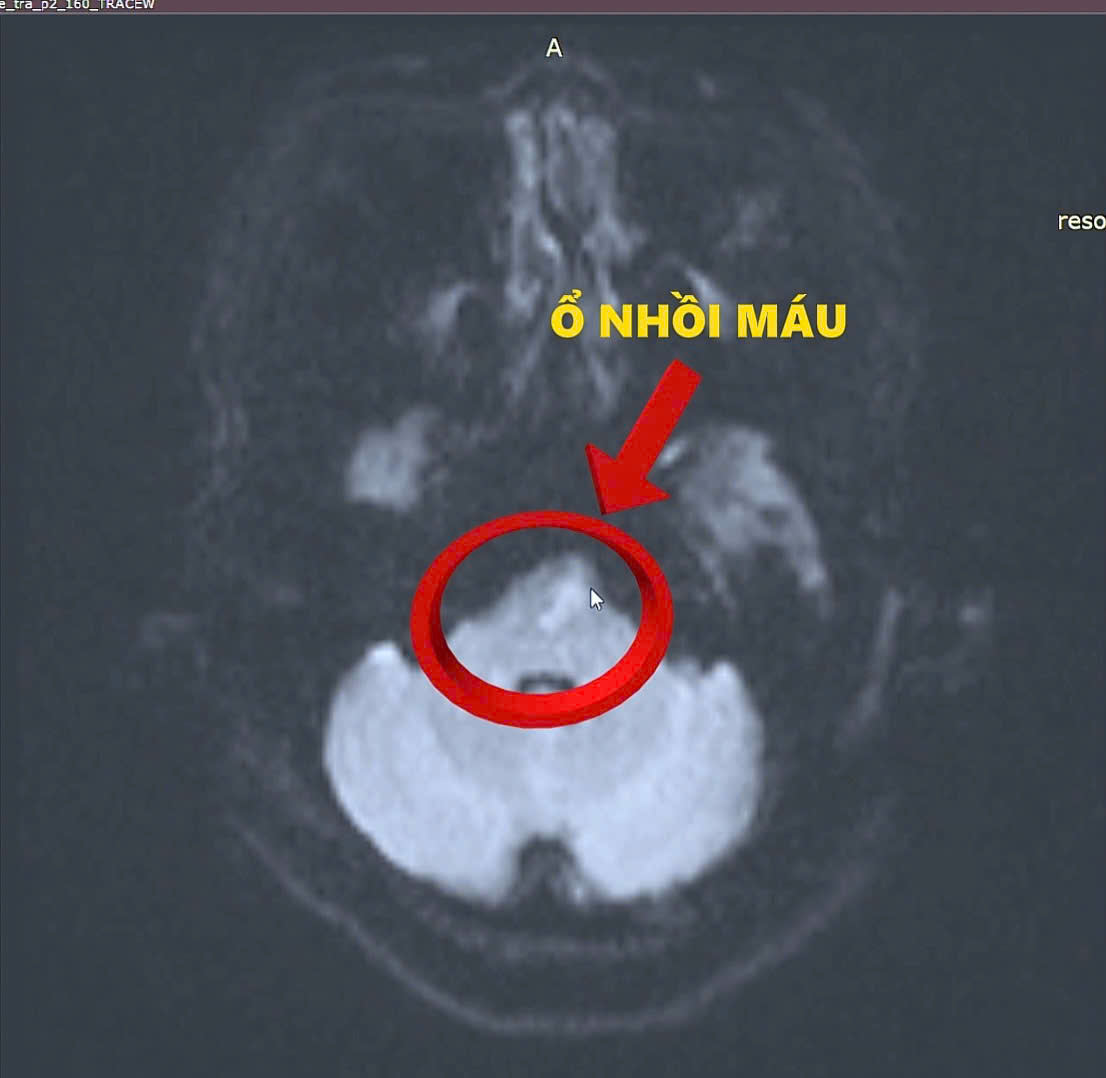

Đột quỵ không phải dấu chấm hết! Tại Bệnh viện Đa khoa Tâm Minh Đức, nhiều bệnh nhân nhồi máu não đã hồi phục trên 90% nhờ tiêm thuốc tiêu sợi huyết đúng giờ vàng.

Phát hiện sớm – Đến viện sớm – Can thiệp đúng giờ vàng chính là chìa khóa cứu não, cứu người.